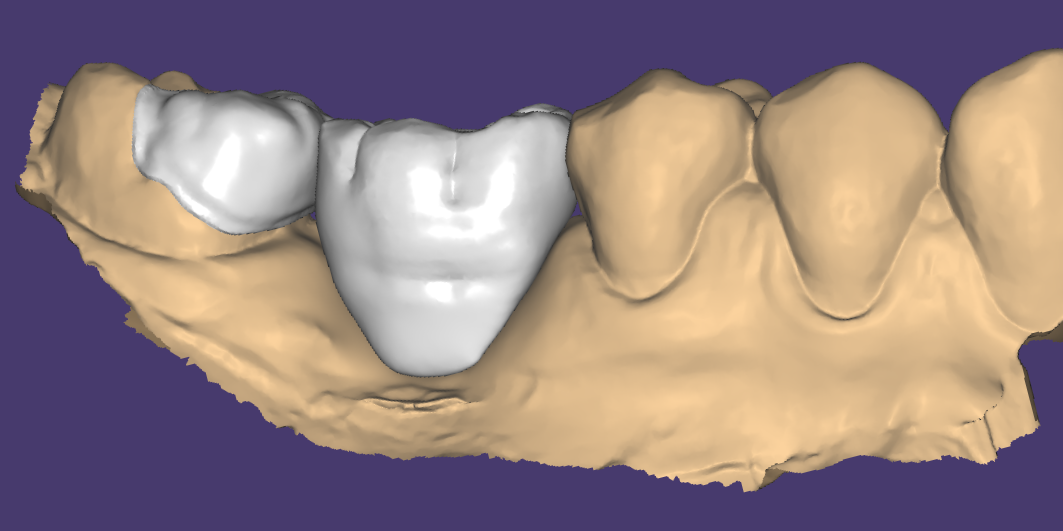

Relativement récents, les bridges collés cantilever postérieurs constituent une alternative fixe, fiable et véritablement minimalement invasive aux implants dans les secteurs postérieurs. Cette thérapeutique qui repose sur des indications bien précises est parfois débattue avec passion sur les réseaux sociaux ou dans les congrès scientifiques. Cependant des études cliniques existent, tout comme des recommandations validées dans des journaux internationaux. Leur succès repose sur des préparations et des principes biomécaniques rigoureux, pourtant simples à intégrer au quotidien. Cette intervention propose un guide clair et opérationnel incluant indications, étapes clés, protocoles d’adhésion et réglages occlusaux pour les mettre en œuvre avec confiance et reproductibilité.